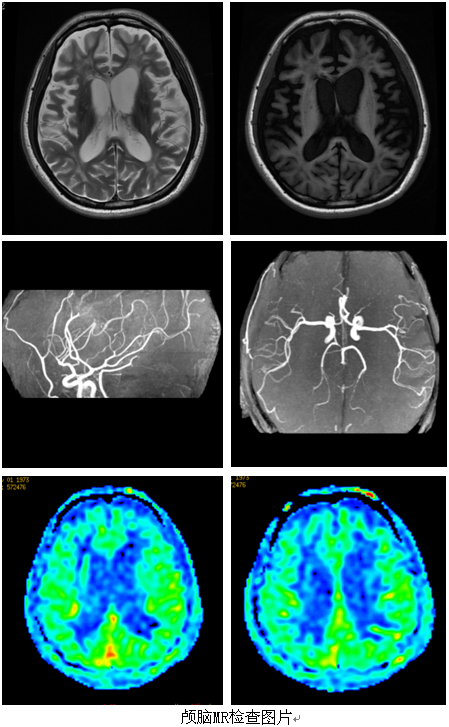

42岁的程某2015年1月由于一氧化碳中毒致昏迷,在当地医院行综合治疗后未恢复意识,被宣告不治。辗转来到广东三九脑科医院康复医学科主任后,医生通过核磁共振等相关检查发现,颅脑MR:脑内多发异常信号影及弥漫性脑萎缩(幕上明显),考虑一氧化碳中毒性脑病后遗改变;双侧大脑中动脉M1段走行僵直,分支减少。ASL:双侧额叶大片状低灌注区;双侧颞顶叶小片状稍低灌注改变。